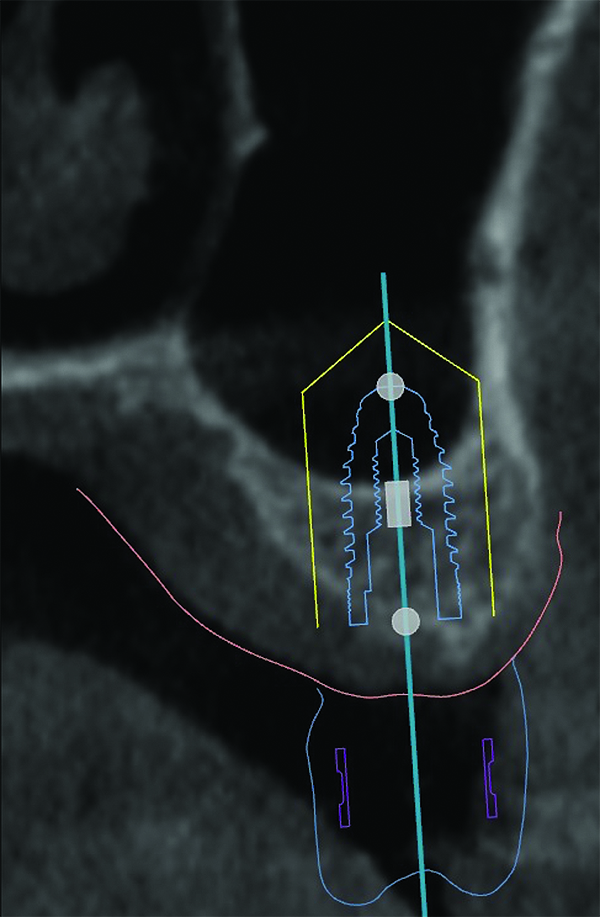

3D radiographic files (CT, CBCT) are stored digitally using a standardized digital imaging and communication in medicine (DICOM) format. In combination with a radiographic guide fabricated from a diagnostic wax-up, CBCT can be used to plan implant location and angulation based on prosthetically driven parameters and local bone/tissue constraints (Figure 8 through Figure 11). Currently, there are two different protocols to incorporate the radiographic guide in 3D scans and to perform computer guided surgery. The first is the double scan protocol, in which the patient wearing the radiographic guide and the radiographic guide alone are scanned separately. Fiduciary markers incorporated in the radiographic guide allow for matching of the two scans. This protocol allows for digitization of the surgical guide with great accuracy, irrespective of errors introduced by patient scans.18 Specialized software can be used to create a surgical guide (Figure 12).

(8) The use of CBCT and digital software for implant treatment planning. The radiographic guide in combination with a 3D CBCT was used to help plan implant position and location.

Figure 8

(9) The use of CBCT and digital software for implant treatment planning. The radiographic guide in combination with a 3D CBCT was used to help plan implant position and location.

Figure 9

(10) The use of CBCT and digital software for implant treatment planning. The radiographic guide in combination with a 3D CBCT was used to help plan implant position and location.

Figure 10

(11) The use of CBCT and digital software for implant treatment planning. The radiographic guide in combination with a 3D CBCT was used to help plan implant position and location.

Figure 11